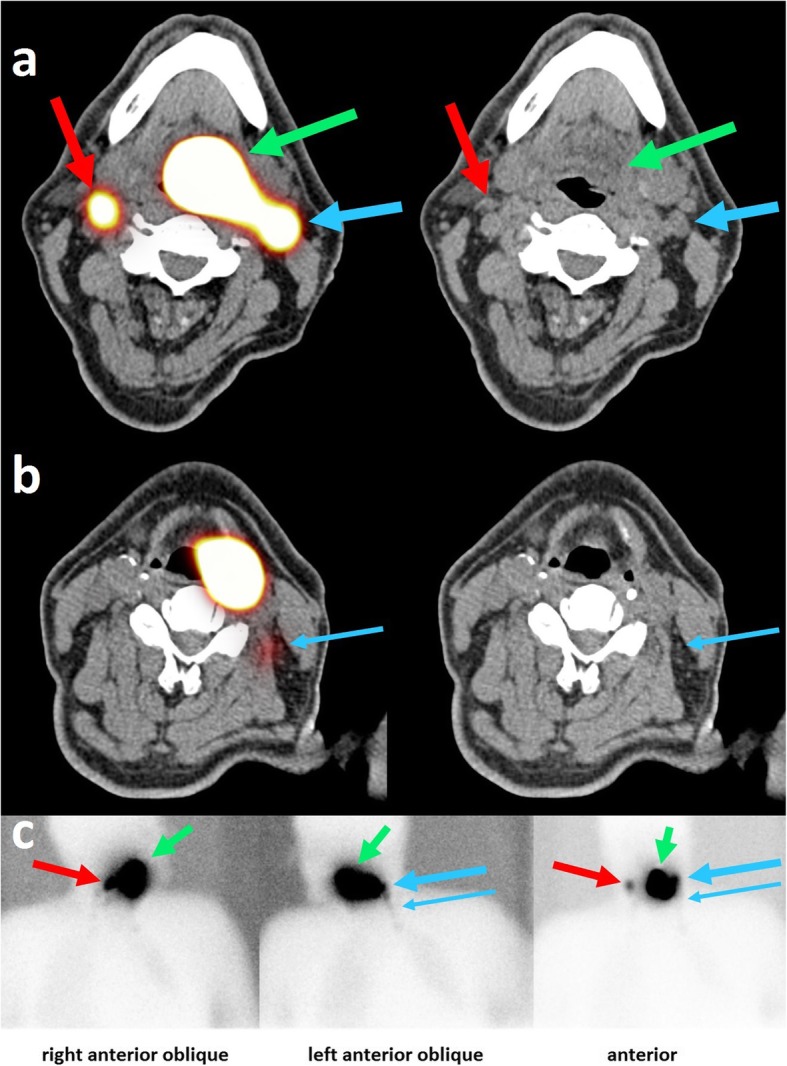

Fig. 3.

Example of SPECT/CT images. SPECT/CT images (a, b) and planar lymphoscintigraphy images (c) of a 64 year old patient with a T1 N1 base-of-tongue carcinoma. Fused SPECT/CT images are shown on the left panel, CT images are shown on the right panel. On the SPECT/CT images, 99mTc-nanocolloid tracer accumulation is visible, indicating the primary tumor (green arrow), the first ipsilateral draining area in level 2 (large blue arrow), and the decreasing tracer activity down the ipsilateral nodal chain into level 3 (small blue arrow). Furthermore, a contralateral draining area is visible in level 2 (red arrow). In the SUSPECT-2 study, this patient would be a candidate for a contralateral sentinel node procedure on the same day as the lymph drainage mapping. On the CT images, the arrows point to the lymph nodes that are thought to be the anatomical substrates that correlated with tracer accumulation